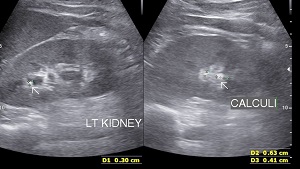

• Sonography: Sonography can show presence of renal calculi, their number, size, location with signs of obstruction.

• Renal Calculi: